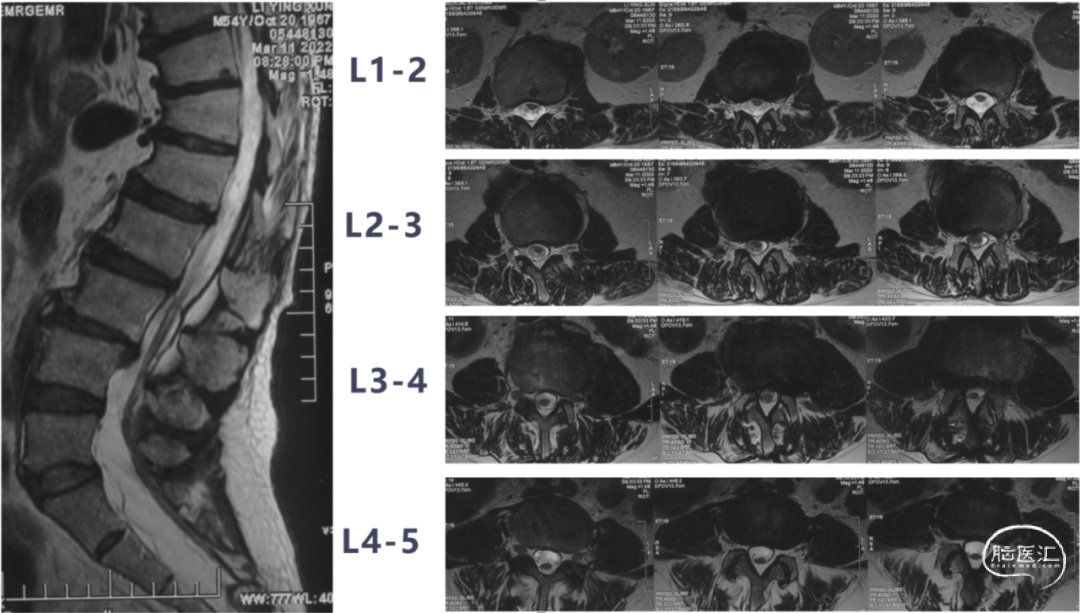

入院前影像学检查

外院术前MR

本次术前MR